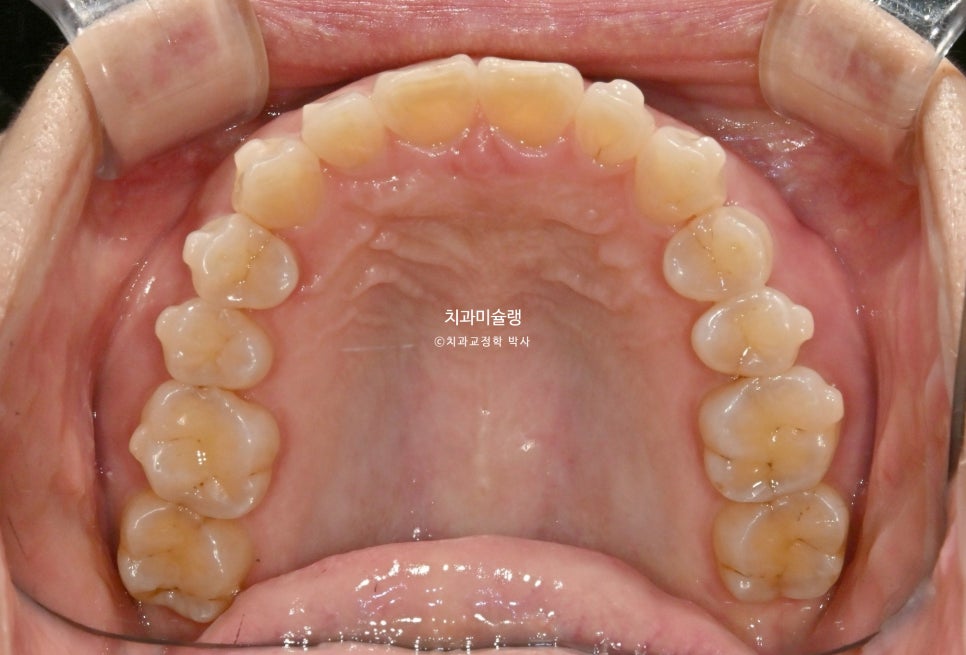

초진 시 구강 상태 분석

환자기준 우측 치아들이 내려와 있습니다. 앞니가 깊게 물리는 과개교합 입니다. 중심선 불일치도 보입니다.

어금니 교합은 좋은편.

앞니가 삐뚤합니다.